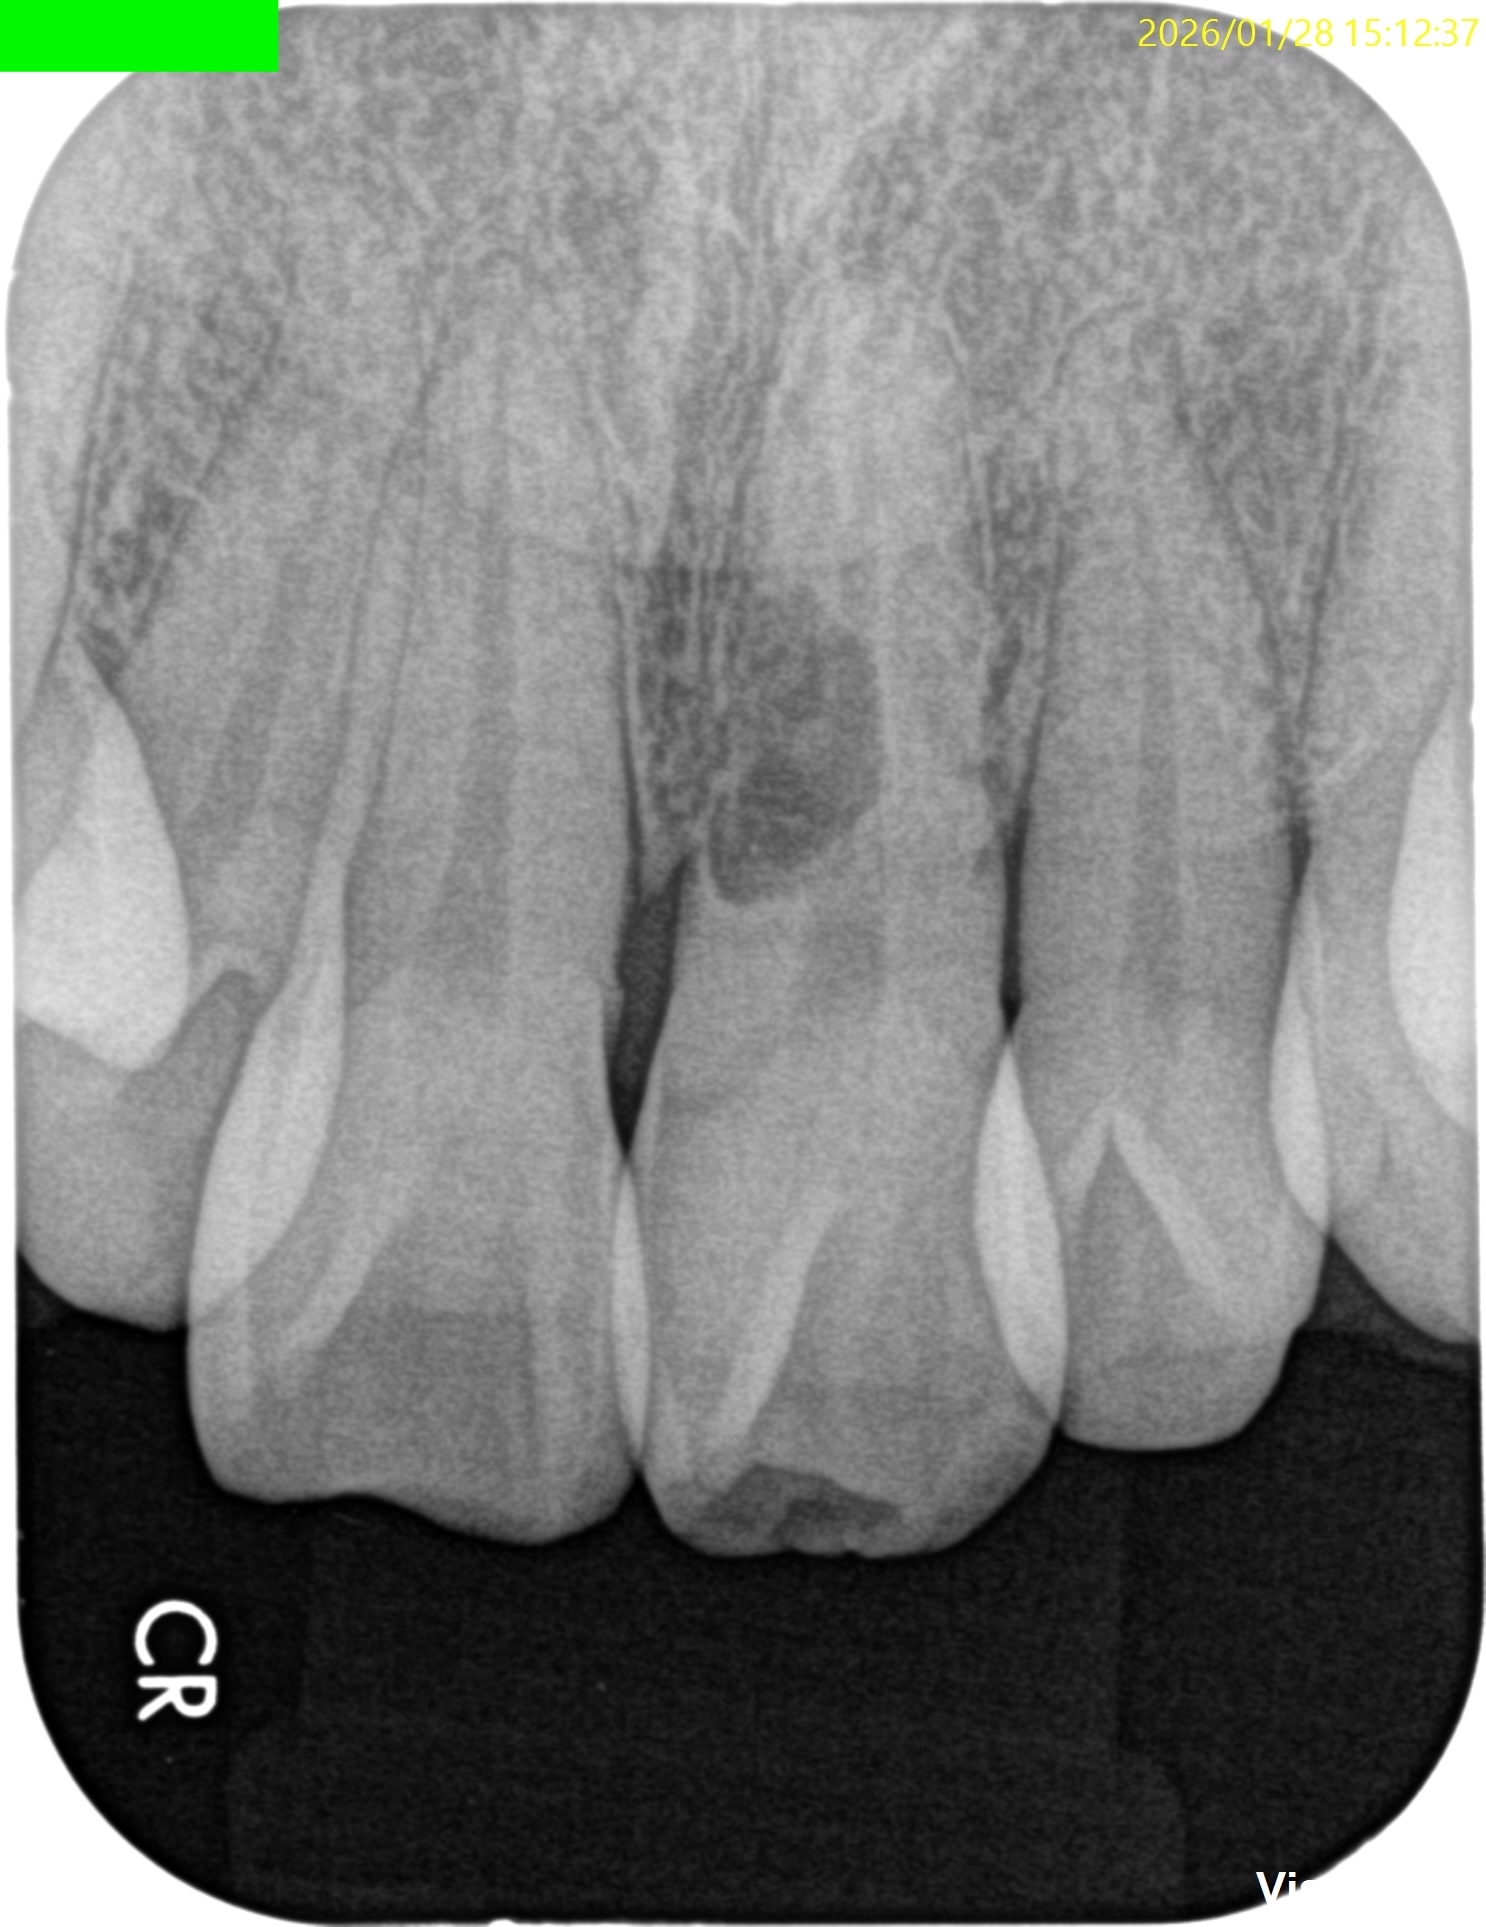

Pre-op Endo Test(2026.1.28)

#9の頬側に大きな穴がある。が、根尖病変はない。

患者さん曰く、かつて脱落した歯を戻した(再植した)という。

根完成永久歯の再植後に、歯髄のRevascularizationは起きないことから本来は根管治療が必要だが、それがなされていないことからこの病態が発生したのかもあしれない。

根管治療して、支台築造して、外部吸収のRepairだが、

根管治療すると外部吸収部位が薄皮一枚で交通しているのがネック

だ。